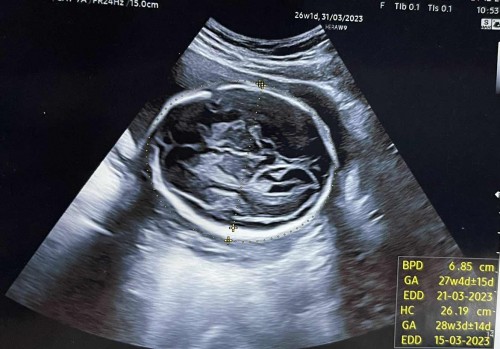

ขอดูรูปซาวด์ส่วนกระโหลกทีจ้า ตอนนี้26 วีค

ตอนนี้26วีค ของเราหมอแจ้งว่าน้องกระโหลกหนาให้ไปรพ.ใหญ่อีกที เราลองเทียบของเพื่อนและเปลี่ยนคลินิคหมอบอกปกติ แต่เราก็ยังเครียดที่หมอคนแรกทักค่ะ ขอดูของแม่ๆทีจ้า (ใบที่มีเขียนว่าBPD)#ท้องแรกคะ #ขอบคุณล่วงหน้านะคะ #คุณแม่ๆช่วยแนะนำหน่อยค่ะ